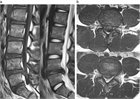

1. ヘルニアのサイズが大きいものや、遊離脱出したものや、MRIでリング状に造影されるものは高率に自然退縮する(ガイドライン推奨grade B)。